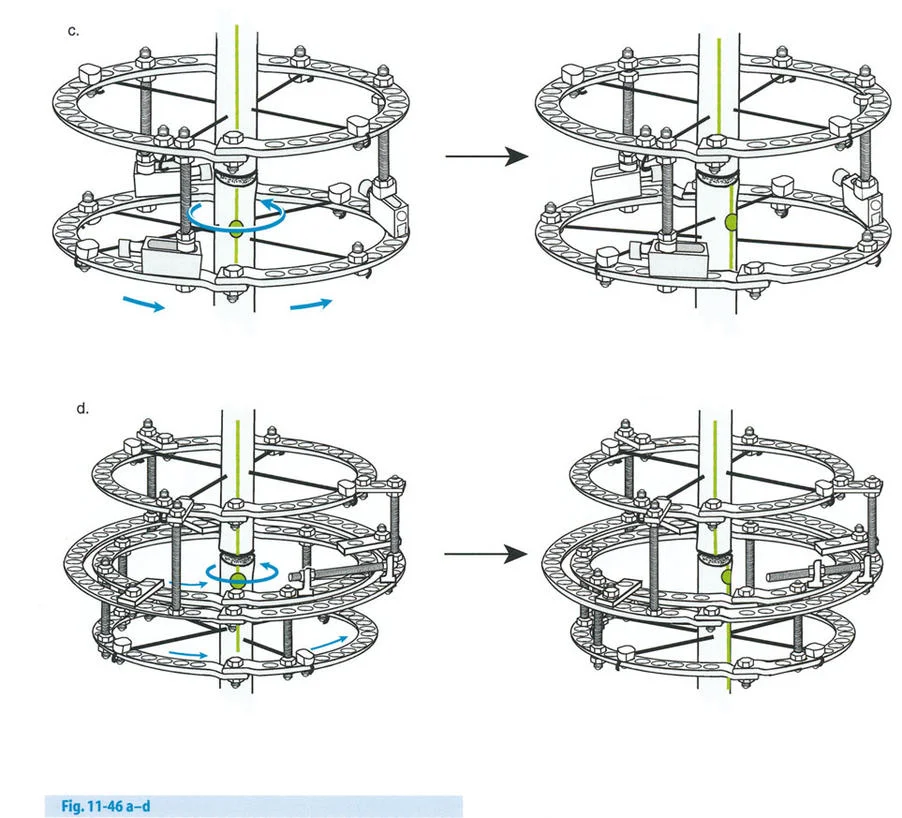

- مثبتات إليزاروف الدائرية الكلاسيكية: تتكون من حلقات معدنية متصلة بالعظم بأسلاك رفيعة، وتسمح بتصحيح متعدد المستويات.

- أنظمة الهيكسابود الحديثة (مثل جهاز تايلور الفراغي Taylor Spatial Frame): تستخدم ست دعامات متداخلة (struts) متصلة بحلقتين. يتم التحكم فيها بواسطة برنامج حاسوبي يقوم بحساب التعديلات اليومية بدقة فائقة لتصحيح التشوه في ستة اتجاهات.

لمطابقة مفصلة المثبت الخارجي مع المستوى الدقيق لمركز دوران الانحراف (CORA)، يجب غالبًا بناء المفصلة فوق أو تحت مستوى الحلقة الفعلية. يُعرف هذا في مبادئ بالي باسم تجميع المفصلة القريبة من المفصل (juxta-articular hinge assembly).

إذا كان مركز دوران الانحراف (CORA) يقع بالقرب من خط المفصل، فإن وضع حلقة إليزاروف القياسية عند هذا المستوى بالضبط مستحيل دون انتهاك مساحة المفصل أو شد الهياكل الكبسولية الحيوية. لذلك، يتم تثبيت الحلقة المرجعية بالعظم الكثيف أو العظم الطويل المتاح، ويتم بناء آلية المفصلة باستخدام قضبان ملولبة، ولوحات توصيل، ودعامات. ثم يتم "إنزالها" (أو رفعها) لتتطابق تمامًا مع مركز دوران الانحراف (CORA) الهندسي الحقيقي.

في المنشآت القريبة من المفصل، غالبًا ما نعتمد على قاعدة قطع العظم 2. نظرًا لأنه لا يمكننا قطع العظم بأمان عند خط المفصل تمامًا (مركز دوران الانحراف CORA)، فإننا نقطع العظم في مستوى أدنى في منطقة الميتافيسيس. بعد تحقيق التصحيح الزاوي عبر المفصلات (محور تصحيح الانحراف ACA)، يتم إعادة محاذاة خطوط المحور الميكانيكي بشكل مثالي، ولكن نهايات العظم في موقع قطع العظم تتحرك بالنسبة لبعضها البعض.